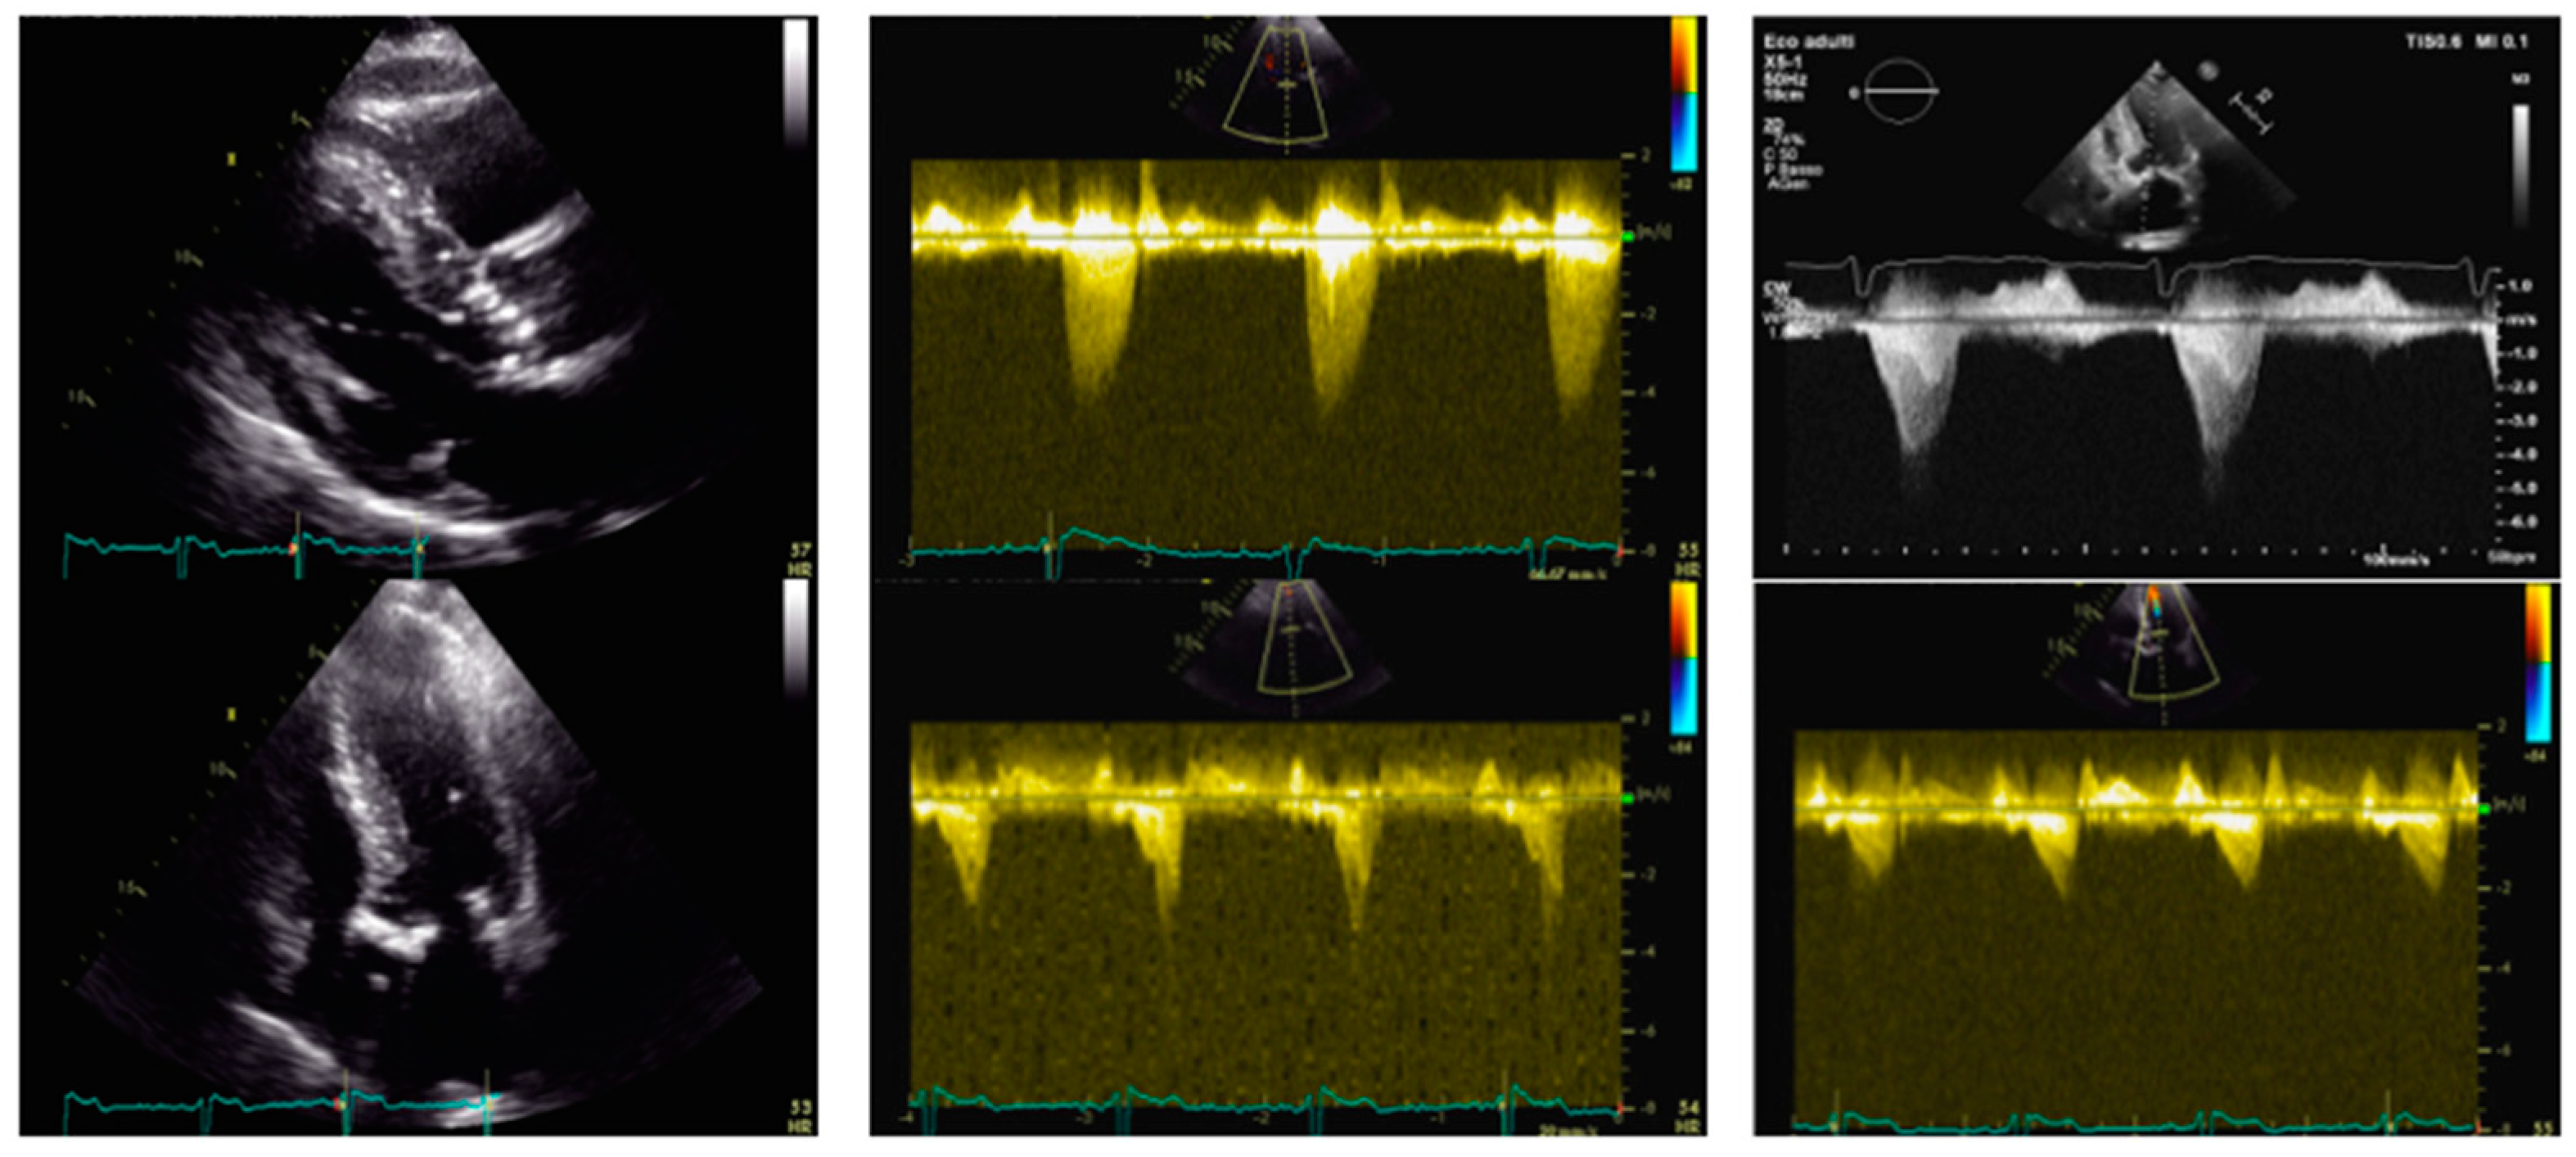

Figure 2. Transthoracic and transesophageal echocardiography in an 86-year-old woman before and after aortic valve stenosis percutaneous treatment and transcatheter alcohol septal ablation. Left panel: PLAX view (upper) and 4-chamber view (lower); IVS = 26 mm; LVEDVi = 45 mL/mq. Central panel: aortic valve peak velocity of 5.8 m/s (upper) with a mean gradient of 77 mmHg and dynamic LVOT gradient (lower) of 65 mmHg. Right panel—after TAVI and alcohol septal ablation: dynamic LVOT gradient (upper) of 20 mmHg but evidence of residual SAM of the anterior mitral leaflet (lower) by TEE. IVS: interventricular septum. LVEDVi: left ventricular end-diastolic volume indexed. LVOT: left ventricular outflow tract. SAM: systolic anterior motion. TAVI: transcatheter aortic valve implantation.

The pre-procedural TTE revealed a marked HLV (IVS 26 mm, posterior wall (PW) 11 mm), non-dilated, with preserved systolic function (EF 56%) and no regional wall motion abnormalities. An LVOT dynamic obstructive gradient up to 65 mmHg was found. AS was noted (maximum gradient 135 mmHg, mean gradient 77 mmHg, Vmax 5.8 m/s, continuity equation not applicable due to subvalvular gradient, planimetric area 0.7 cm2), along with mild MVR. Cardiac catheterization showed no coronary arteries stenosis, but a combined pulmonary hypertension. The case was collegially discussed by the Heart Team and the surgical approach was excluded due to an STS score of 9% and a EUROscore II of 8%.

The patient underwent TAVI with a 25 mm Navitor bioprosthesis implantation. During the procedure, volume expansion and a continuous esmolol infusion of up to 50 mcg/kg/min were administered. Post-procedural left catheterization confirmed the persistence of LVOTO with a dynamic gradient of 40 mmHg. Severe MVR emerged, with increased pressures in the left ventricle. The postprocedural TTE demonstrated a gradient of 67 mmHg and a significant MVR caused by SAM of the AML. Due to the patient’s hemodynamical instability, transcatheter alcohol septal ablation was performed.

Under general anesthesia and intubation, with TEE guidance, septal branches S2 and S3 were alcoholized, and S1 was embolized using coils. Myocardial perfusion was monitored using a SonoVue echo-contrast agent. After the procedure, the LVOT gradient was reduced to 15 mmHg and MVR was trivial. The subsequent TTE confirmed a persistent subvalvular gradient of 20 mmHg and a residual SAM of the chordal structures, resulting in mild MVR. Despite the improvement in hemodynamics, the patient died a few days later due to infectious complications.